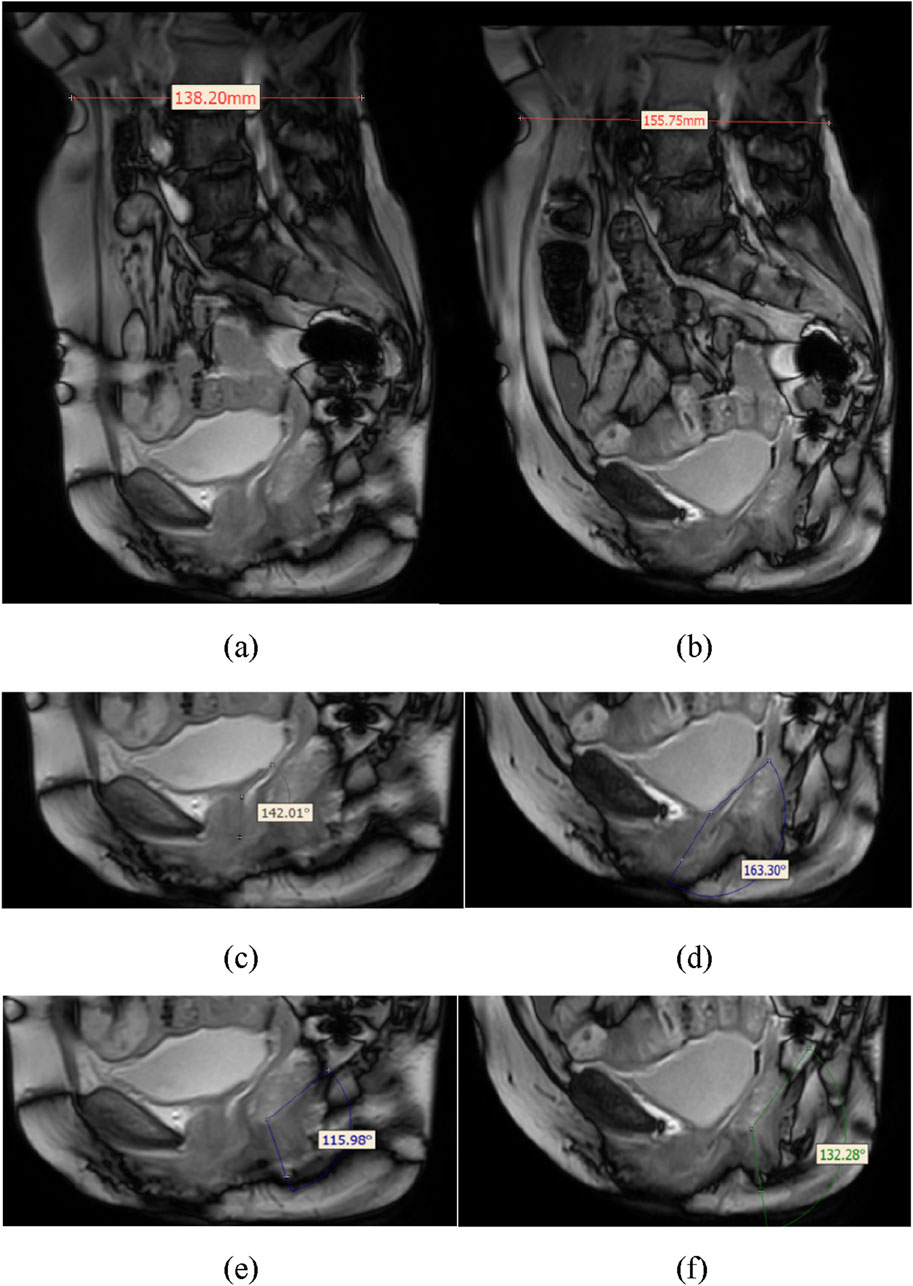

Objective: This study aims to utilize finite element analysis (FEA) to explore the effects of different rehabilitation training methods on the ability of elderly women to maintain urinary and fecal control. It also seeks to determine the muscle prioritization during pelvic rehabilitation training, providing a scientific basis for personalized rehabilitation nursing. Methods: A 3D pelvic-thigh modeling was constructed based on CT and MRI images from a 70-year-old Chinese elderly female volunteer. Model validity was verified by assessing relative changes in waist circumference, RVA, and ARA against imaging measurements, with geometric deviations controlled within 10%. The material properties of the muscles were altered to simulate the effects of five different physical rehabilitation methods. By comparing changes in the retrovesical angle (RVA) and anorectal angulation (ARA) under different muscle material properties settings, the relationship between rehabilitation training methods and urinary and fecal control was quantified. Results: The constructed model demonstrated high geometric consistency with pelvic floor anatomy, showing less than 8.28% deviation from imaging-based measurements. As muscle material properties improved, the RVA gradually decreased, and the ARA gradually increased, approaching normal ranges. The results highlight the critical roles of the levator ani, pelvic floor, rectus abdominis, erector spinae, and hip muscles. Conclusions: The findings from this simulation indicate the potential efficacy of rehabilitation training in supporting urinary and fecal control. The study emphasizes the importance of personalized pelvic floor rehabilitation programs based on gender differences, muscle status, and dysfunction types, offering new perspectives and possibilities for using FEA in elderly populations. Nevertheless, the findings are derived from a single-subject model and computational simulations without direct clinical validation, which may limit generalizability.